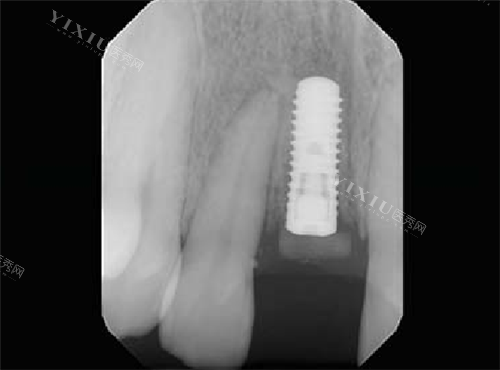

临床对比:传统SLA表面植体需6-12周完成骨结合,而瑞锆植体需要4-8周。北京某口腔医院的数据显示,采用瑞锆植体的即刻种植病例,初期稳定性达标率从78%提升至92%。

患者病例:52岁的张女士因牙周病需拔除前牙,选择瑞锆植体实现“拔牙即种”。她描述:“手术当天就能戴临时冠,两周后吃苹果完全没异样感,比预期快了一倍。”